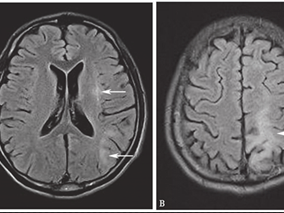

1小时条评论【病例资料】 患者,女性,33岁。因四肢麻木无力、言语不清2个月于2012年5月10日收入院。 现病史:患者2个月前出现双手及双膝关节以下麻木、无力,行走不稳,言语不清,反应迟钝。偶有头痛、呕吐、饮水呛咳。无头晕、耳鸣,无发热、抽搐。当地医院就诊,头颅CT检查...